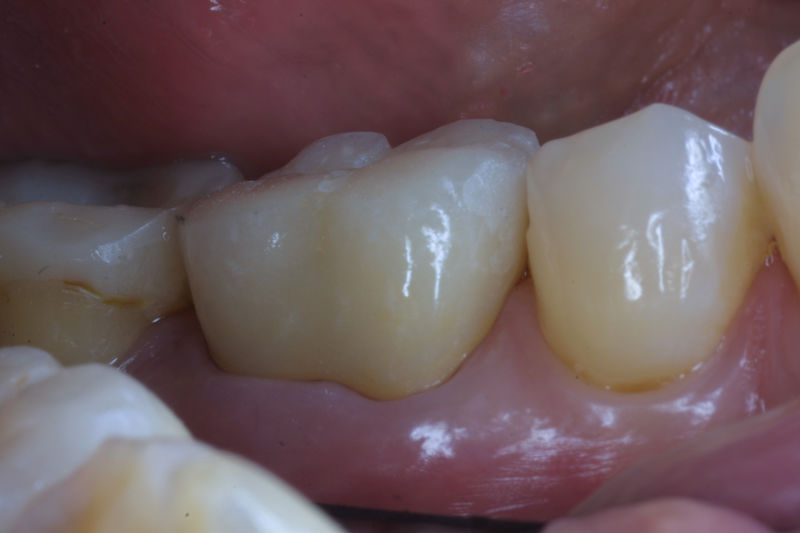

Restauraciones fabricadas en el laboratorio con materiales estéticos, los cuales cubren de manera parcial dientes posteriores. Se utilizan primariamente para restaurar dientes con caries, fracturas y/o defectos amplios. Para poder enviar el caso al laboratorio se toman impresiones utilizando materiales de impresión o técnicas modernas digitales.

Restauraciones fabricadas en el laboratorio con materiales estéticos, los cuales cubren de manera total dientes anteriores y posteriores. Se utilizan primariamente para restaurar dientes con caries, fracturas y/o defectos amplios, así como soportes de puentes. Para poder enviar el caso al laboratorio se toman impresiones utilizando materiales de impresión o técnicas modernas digitales.